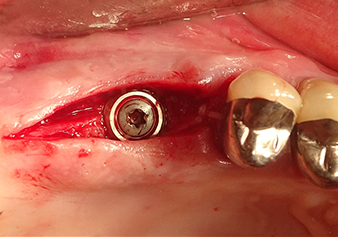

The I2A instrument (diameter 2.0 mm) was then used to perforate the sinus floor intermittently and on the smallest scale possible. This special piezosurgical method ensures that the Schneiderian membrane is not damaged. When the Z25P was used, the membrane was already lifted slightly by the coolant supplied via the instrument tip (Fig. 3). The coolant quantity was just 50% in order to avoid high pressure in the implant bed.

Implant bed preparation and augmentation

Following an intermediate check (Fig. 4) a further preparation step was performed (Fig. 5). Afterwards, the hydraulic Z35P instrument was used to lift the membrane to the desired position (Fig. 6 and 7). This was followed by further piezosurgical preparation of the implant bed, concluded with a rotary bur and shoulder milling cutter up to the implant diameter of 4.8 mm. Before the implant was inserted, the augmentation material (particle size approx. 0.8-1.6 mm) was introduced underneath the Schneiderian membrane (Fig. 8).